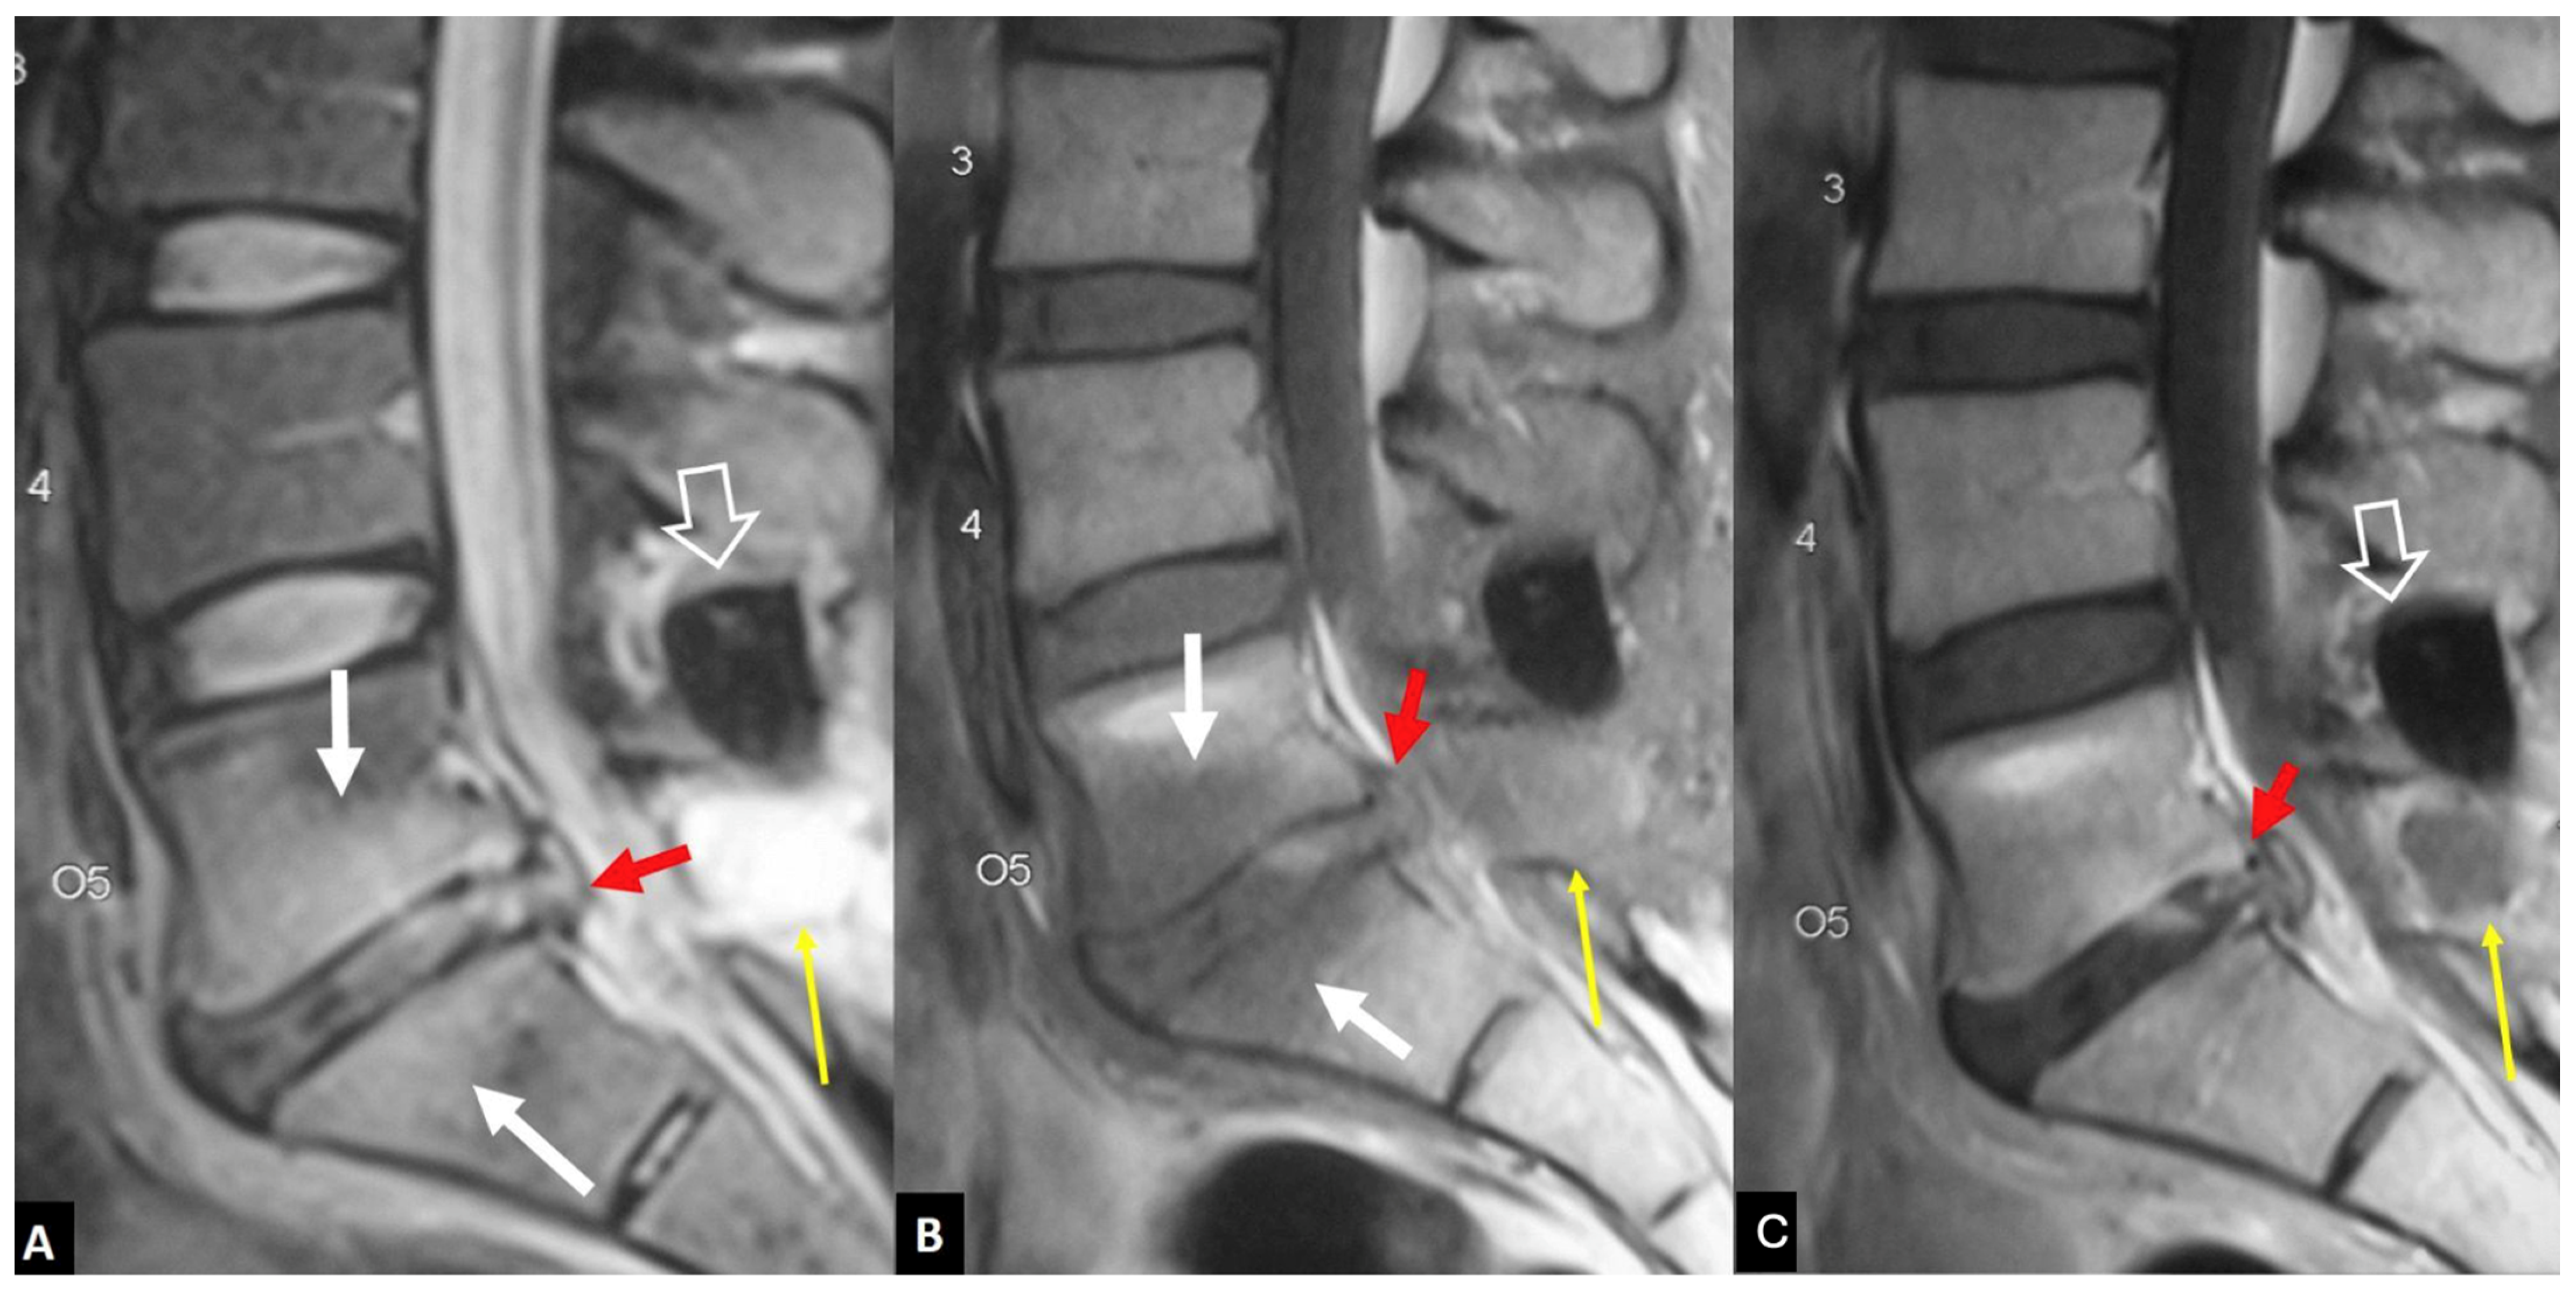

2.1.4. Destructive Spondyloarthropathy

2.1.6. Post-Operative Aseptic Discitis

2.1.7. Trauma

- Kim, S.-K.; Shin, K.; Song, Y.; Lee, S.; Kim, T.-H. Andersson lesions of whole spine magnetic resonance imaging compared with plain radiography in ankylosing spondylitis. Rheumatol. Int. 2016, 36, 1663–1670. [Google Scholar] [CrossRef] [PubMed]

- Madsen, K.B.; Jurik, A.G. MRI grading method for active and chronic spinal changes in spondyloarthritis. Clin. Radiol. 2010, 65, 6–14. [Google Scholar] [CrossRef]

- Park, Y.-S.; Kim, J.-H.; Ryu, J.-A.; Kim, T.-H. The Andersson lesion in ankylosing spondylitis: Distinguishing between the inflammatory and traumatic subtypes. J. Bone Jt. Surg. Br. 2011, 93, 961–966. [Google Scholar] [CrossRef]